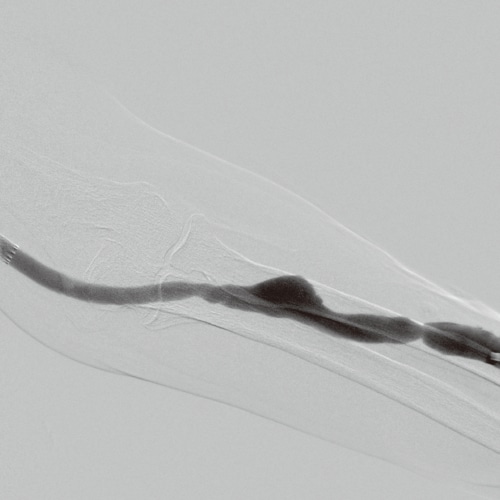

DSA

The DSA and roadmap functions make it suitable for intravascular procedures.